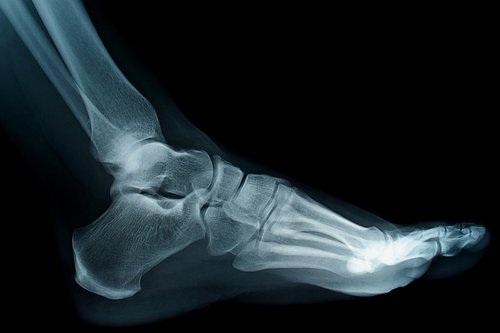

Cirugía Podológica

Somos especialistas en cirugía podológica con formación en los EEUU.

Cuando la sintomatología no mejora con el tratamiento conservador disponemos del tratamiento quirúrgico y definitivo.